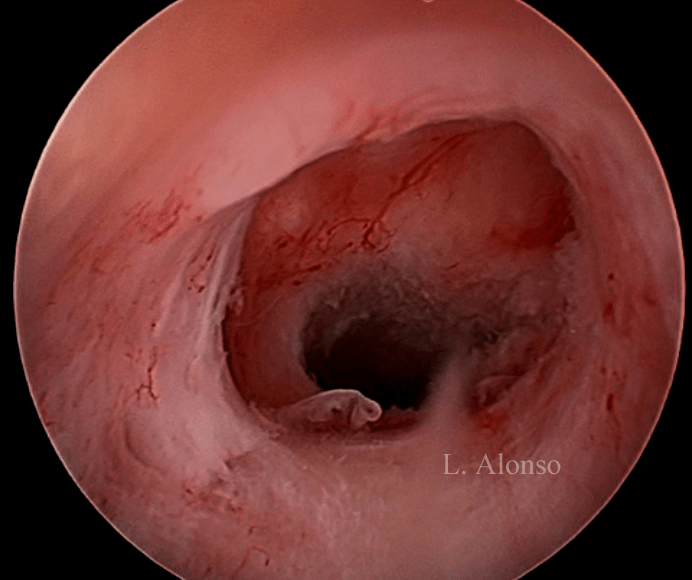

Hysterosonography enhance visualization of the isthmocele even when there is no blood accumulation inside of it. Hysteroscopy is the “Gold Standard” technique for the diagnosis of isthmocele. Hysteroscopy allows direct visualization of the anterior and posterior borders of the isthmocele that some authors define as an anterior and a posterior arch, the isthmocele is actually the area contained between these two arches.

The hysteroscopic repair of a cesarean scar is frequently referred as Isthmoplasty. The surgical technique first described by Fernandez in 1996 at the 25th annual meeting of the AAGL (5), consists of remodeling the sac “flattening” the area of the isthmocele from the lower arch to the external cervical os. The surgical procedure must be performed extremely carefully and very superficially, taking into account that the dome of the isthmocele is in close contact with the bladder

and the lateral areas of the defect with the uterine arteries (1). In addition to carrying out the resection of the fibrotic tissue, Fabres favors the treatment of the tissue at the base of the defect by means of the local fulguration of the dilated vessels as well as the inflammatory tissue, responsible for the “in situ” blood production.